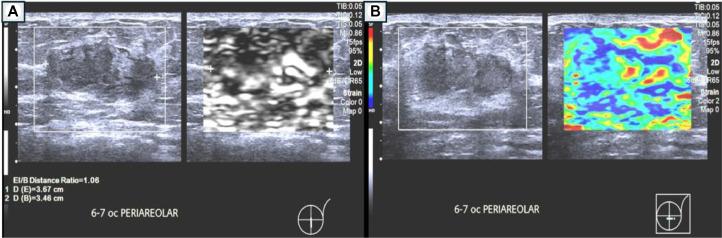

Primary breast tuberculosis is a rare disease under extrapulmonary tuberculosis category. It tends to affect females of reproductive age rather than postmenopausal women or prepubescent girls. This rare form of disease poses a challenge in diagnosing as imaging can mimic the appearance of both benign and malignant breast lesions. We describe a case of primary breast tuberculosis in a young female who presented with a persistent left breast lump. and was diagnosed with chronic left breast abscess. Histopathological examination of the lesion was consistent with granulomatous mastitis, secondary to mycobacterium tuberculosis infection. The patient was treated with a 6-month course of anti-tuberculosis drug with complete resolution of the symptoms and the left breast lesion on serial ultrasound imaging.